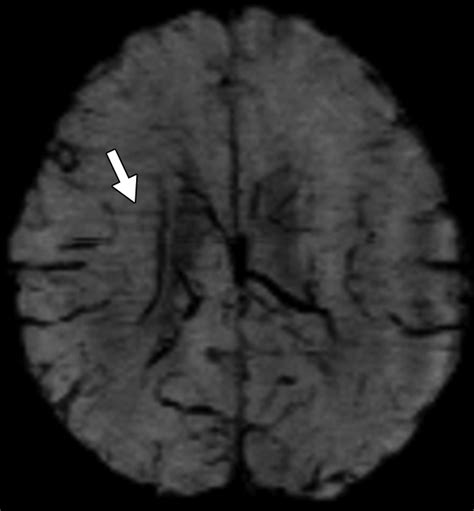

• Traumatic Brain Injury (TBI): SWI is highly sensitive to the detection of Diffuse Axonal Injury (DAI) and microhemorrhages resulting from shear forces during trauma.

Radiologists look for "blooming effects" on the images, where small, dark spots represent paramagnetic substances like blood products. Because the signal decay is accelerated in regions with high iron or deoxyhemoglobin content, these areas appear as dark, high-contrast signals. Interpreting these images requires an understanding of how to differentiate between normal venous blood and pathological hemorrhages. For instance, the presence of blood in deep brain nuclei versus the cortex can indicate vastly different underlying etiologies, such as hypertensive vasculopathy or cerebral amyloid angiopathy.